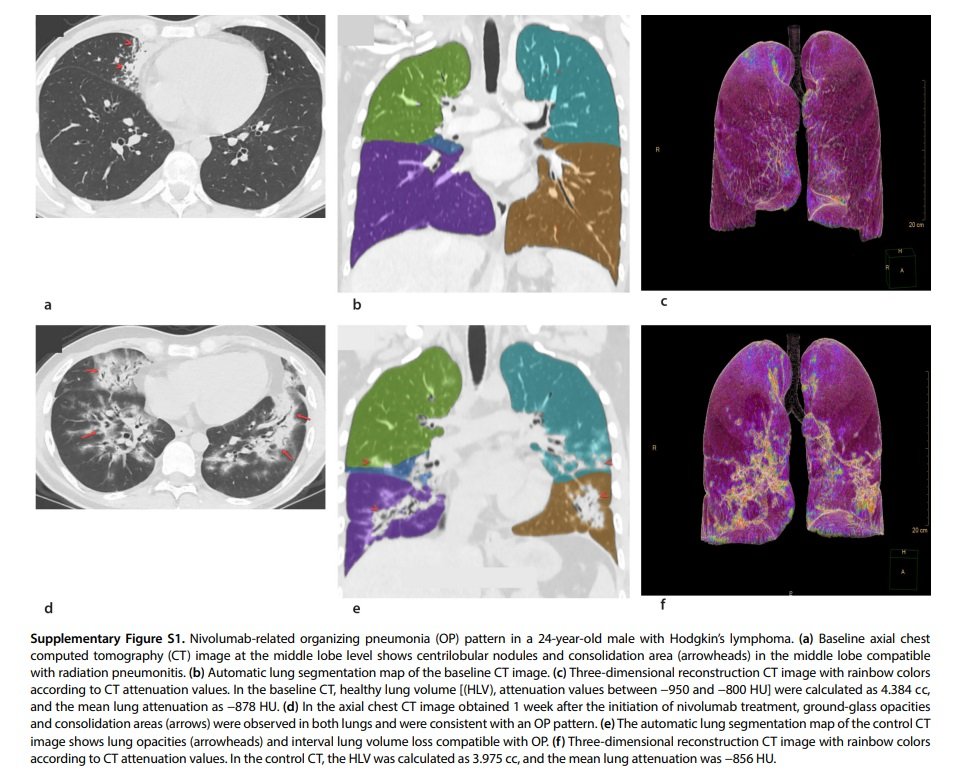

•The OP pattern is a form of acute lung injury and is the most common form of DILD

Although eosinophilic pneumonia (EP) can be present in similar imaging findings with an OP pattern, EP is characterized by peripheral band-like opacities and predominance in the upper lobes